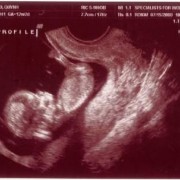

Ngày 11/28/1999 Ba Mẹ có nhau, lúc đó con ở đâu ha? Ngày 5/27/2008, con đây rồi!!! Mới được 2 tuần, là hạt nhân nhỏ xíu trong bụng Mẹ thôi Ngày 6/4/08, lần đầu tiên Ba Mẹ nghe tim con đập, 124 nhịp/phút. Mẹ sung sướng nhìn con. Còn Ba thì rơm rớm nước mắt, hihi!! Ngày 7/8/2008, con được 11 tuần rồi, bắt đầu có tay chân rồi đây... 1 tuần sau tay chân con đã dài ra rồi, lẹ ghê... ...biết nhào lộn vòng vòng nữa, mới nằm úp giờ nằm ngửa rồi. Ngày 9/3/2008, Mẹ chưa muốn biết con là trai hay gái vì muốn bất ngờ, nhưng rồi cuối cùng cũng không đợi được... ...hihi, cục cưng của Ba Mẹ là con trai. Con trai miệng bự giống Ba.  19 tuần là mắt mũi miệng đầy đủ hén. Từ khi biết có con, Mẹ nhờ Ba chụp hình hai mẹ con mình. Cái này là lúc con được 2 tháng trong bụng Mẹ.. ...24 tuần, con bắt đầu cựa quậy lung tung mỗi ngày... ...36 tuần, có lúc Ba Mẹ tưởng đã mất con nhưng con vẫn lớn giỏi ngoan... ..39 tuần, con nặng quá rồi nhưng Mẹ vẫn muốn con ở trong đó thêm chút nữa cho lớn lớn... Ba thì nôn gặp con quá, ngày nào Ba cũng nói chuyện với con.  Bụng Ba cũng bự rồi nè! Ngày 1/20/2009, con 39 tuần, bác sĩ muốn con ra sớm cho an toàn.  Ba Mẹ hồi hộp đợi tới lúc gặp con... Sau gần 8 tiếng chờ đợi thì con ra đời!! Con mở mắt nhìn Mẹ như là biết rồi đó.  Thương con ghê nơi! 1 tuần tuổi thì rụng rún.  2 tuần tuổi thì chụp hình lần đầu với Mẹ, nhỏ xíu xiu xiu... 7 tháng (8/2009) con bò lung tung, chụp hình mà không yên... 14 tháng (4/2010) con chỉ muốn chạy chơi thôi, Ba chụp lẹ lẹ nghe. Ngày 2/19/2010 Ba Mẹ làm lễ cưới ở nhà thờ.  Lần này thì có con rồi.  Có con Ba Mẹ có tất cả...